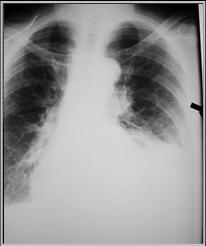

Foramen of Bochdalek Hernia

R3